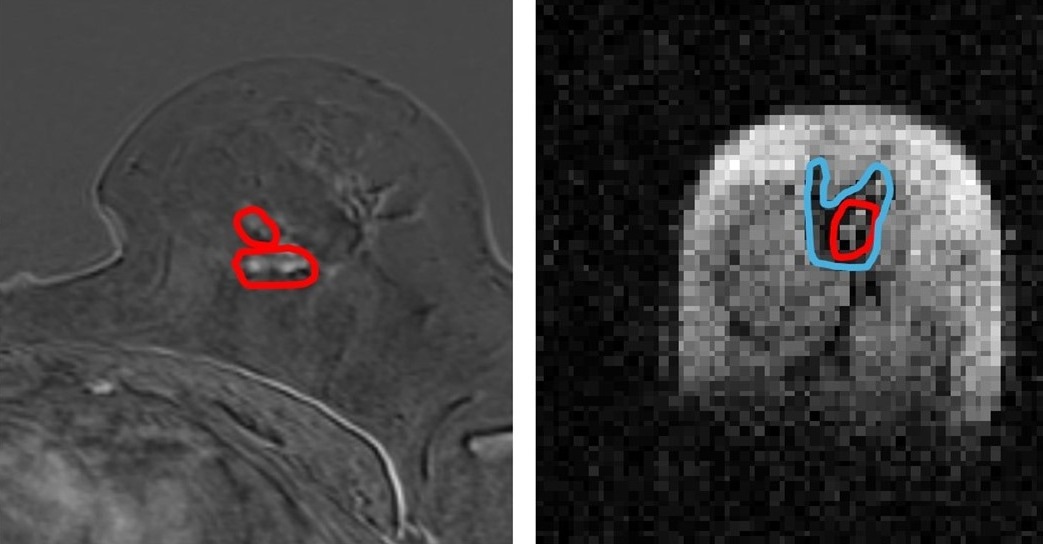

Side by side image of same breast tissue in MRI and FCI. (l) MRI image of breast with cancerous tumours circled in red (r) FCI image of same breast shows same tumour in red with secondary tumour spread in blue. Spread not visible in MRI. The patient had a mixed tumour i.e two different types of tumour and one of them is not visible in MRI. Image Credit: University of Aberdeen

Scientists from the University, in collaboration with NHS Grampian, used a prototype version of the new Field Cycling Imager (FCI) scanner to examine the breast tissue of patients newly diagnosed with cancer. They found that the FCI scanner could distinguish tumor material from healthy tissue with more accuracy than current MRI methods.

This innovation could change the course of treatment for millions of people with cancer.  Currently, around 15 percent of women need a second surgery after a lumpectomy as the edges of the tumor may still be involved. This new technique could potentially more accurately outline these tumors and reduce the need for those repeat operations.